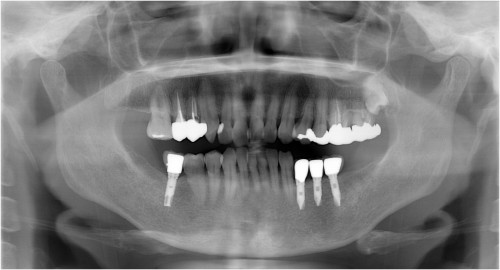

術前

下両奥歯 被せ物装着後